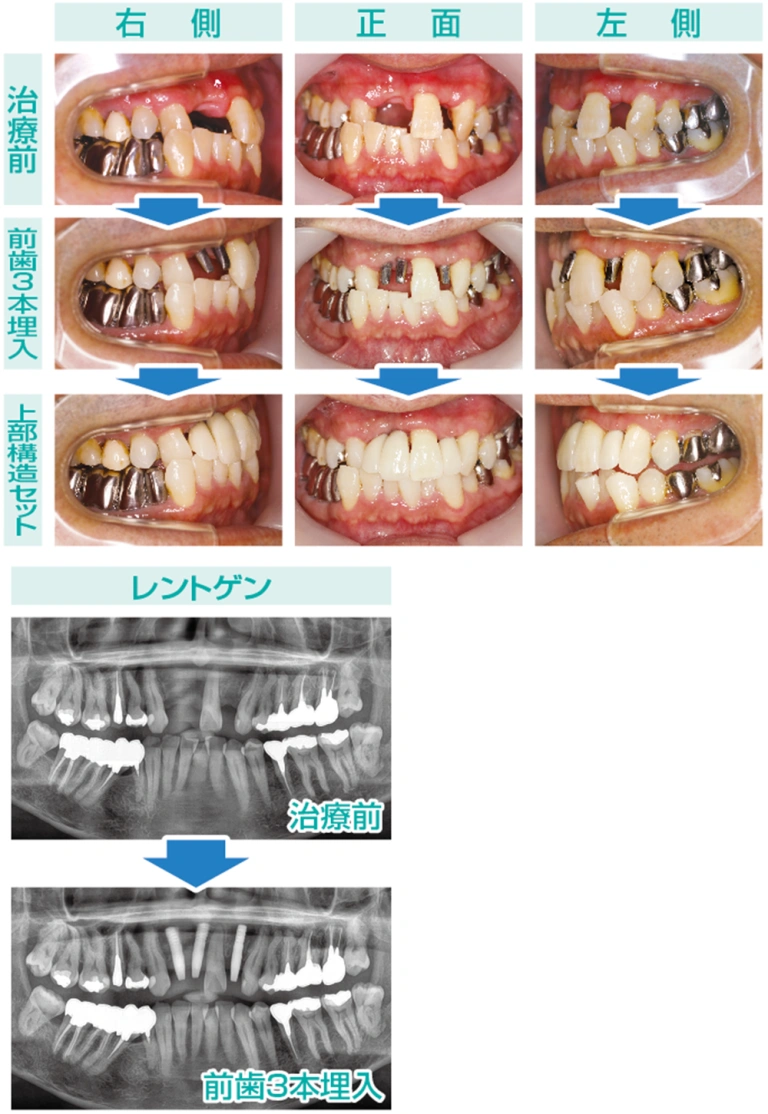

50代男性の今回の症例写真をご覧ください。上顎前歯の3本が欠損しております。そこに3本のインプラントを埋入する場合、特に審美性と機能性の両方を考慮することが重要です。

当院で使用しているAQBインプラントは、直径3㎜の細いインプラントを含むラインナップがあるため、骨の狭いスペースにも柔軟に対応でき、骨量が限られている部位でも有効です。このような選択肢があることで、患者様により適した治療計画を立てることが可能となり、手術の成功率を高めることができます。特に上顎前歯部は審美的な要求が高い部分ですので、インプラントの選択が非常に重要となります。

- 年齢・性別

- 50代 男性

- 治療期間

- 3ヶ月

- 抜歯

- なし

- 治療費

- 1本33万円×3本=99万円

- 治療内容

- 前歯のインプラント補綴

- 施術の副作用(リスク)

- オペによる知覚障害。インプラントによる歯肉炎。インプラント脱落。